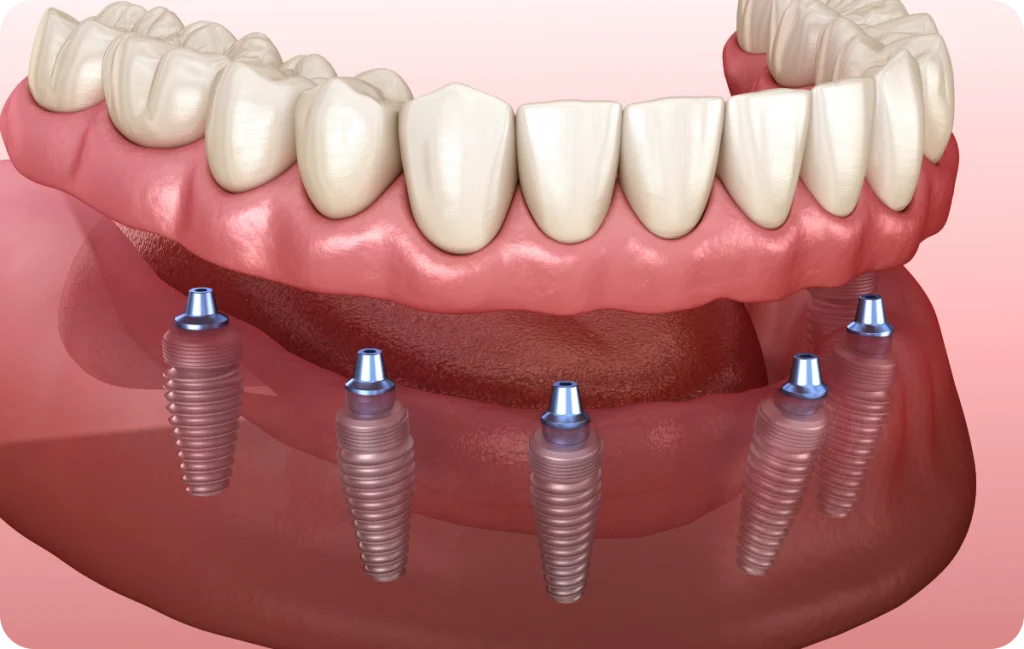

L’All-on-4 / All-on-6 correspond à une approche de remplacement dentaire destinée aux patients présentant une édentation complète ou quasi complète. Concrètement, cette technique repose sur la mise en place d’une prothèse fixe soutenue par des implants dentaires, le plus souvent au nombre de quatre ou de six, positionnés de façon stratégique dans l’os de la mâchoire.

Contrairement aux prothèses amovibles, retirées quotidiennement, l’All-on-4 / All-on-6 s’appuie sur une base fixe solidement ancrée. En effet, les implants jouent le rôle de points de soutien pour une arcade prothétique complète, conçue sur mesure pour chaque patient. De ce fait, cette solution s’adresse principalement aux personnes dont les dents naturelles ne peuvent plus être conservées ou ont déjà été extraites.

La principale différence entre All-on-4 et All-on-6 réside dans le nombre d’implants utilisés pour soutenir la prothèse complète. Dans la technique All-on-4, quatre implants sont positionnés, dont deux implants postérieurs souvent inclinés afin d’optimiser l’ancrage osseux. Cette configuration permet, dans certains cas, d’éviter des procédures complémentaires.

L’All-on-6, quant à lui, repose sur six implants répartis sur l’arcade. Cette option peut être envisagée lorsque le volume osseux le permet et lorsque la situation clinique nécessite une répartition des forces différente.